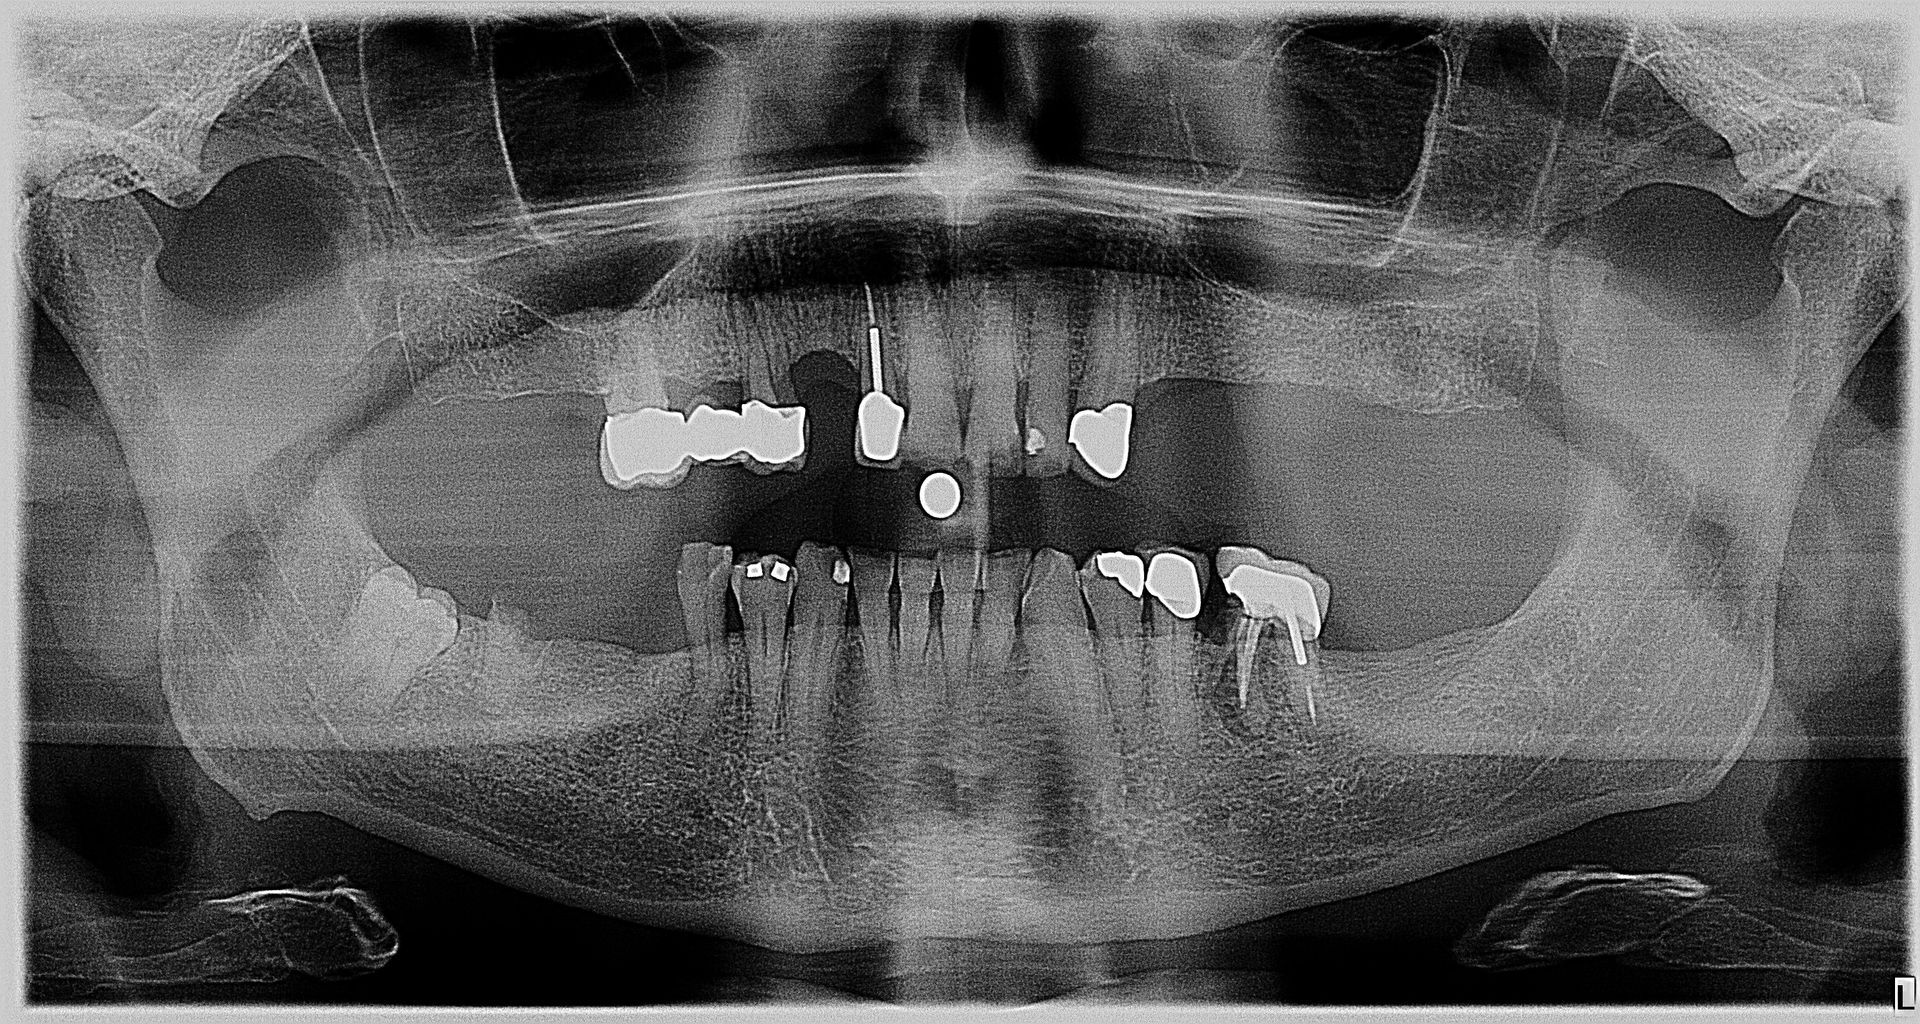

• We do “FULL MOUTH IMPLANT RECONSTRUCTION”

- Full mouth implant reconstruction